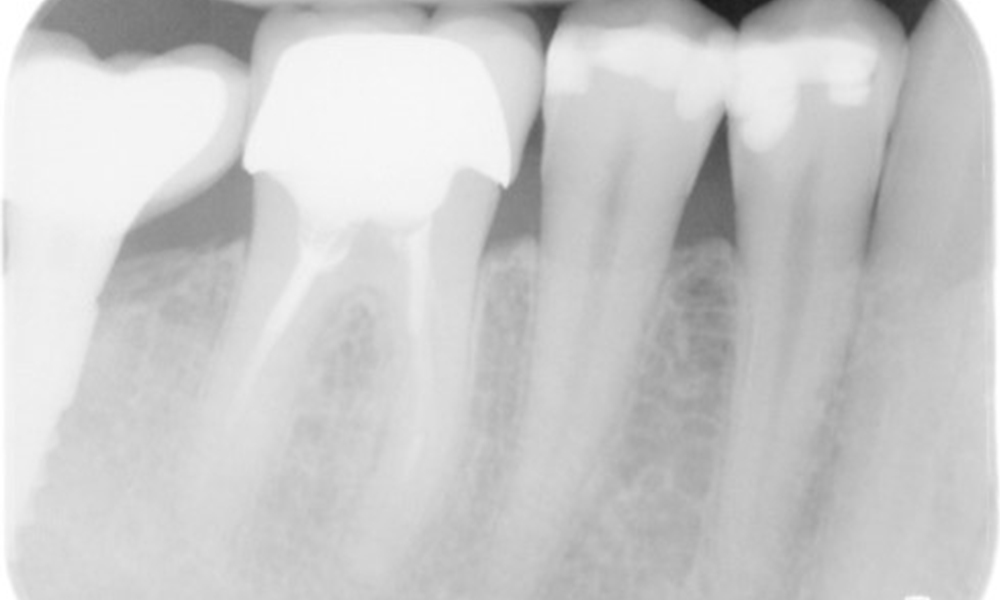

X-ray images (or bitewing X-rays)

X-ray images (or bitewing X-rays) taken on: 18/02/2021